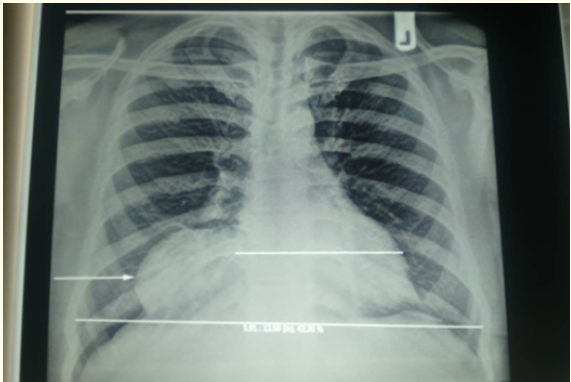

A Rare Giant Pericardial Cyst with Atypical Clinical Presentation- A Case Report

Dabeluchi Chiedozie Ngwu and Nicholas A Kerna